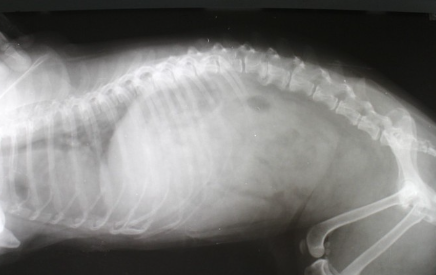

개의 척추는 경추(7개), 흉추(13개), 요추(7개), 선추(3개)와 꼬리꼬리추(6~23개)가 이어져 신체의 축을 형성한다.

척추뼈 안에는 척수가 통과하는 터널 같은 구멍이 있다. 각각의 척추뼈 사이에는 척추를 구부리거나 충격을 흡수하는 쿠션 역할을 하는 조직이 있는데, 이것이 추간판이라고 불리는 것이다.

원래 척추 사이에 잘 자리잡고 있는 추간판이 어떤 박자로 튀어나오거나 밀려난 상태이다.

척추 중앙을 지나는 척수라는 굵은 신경은 뇌에서 꼬리까지 뻗어 있다. 더 나아가 가지가 뻗은 미세한 신경이 온몸에 골고루 퍼져 있다. 추간판이 척수 쪽으로 튀어나와 신경을 압박함으로써 통증, 저림, 마비 등이 발생할 수 있다.

Hansen 1형 디스크는 디스크의 섬유 고리에 균열이 생겨 내부 뇌핵이 탈출하는 유형의 디스크이다. 연골이영양 유전자를 갖고 있는 개는 원래 젤리 모양의 뇌핵 수분이 생후 6개월 이후부터 서서히 빠져나가기 때문에 딱딱해지기 쉽다.

그 결과, 추간판의 두께가 얇아지고 충격 능력이 떨어진다. 이런 식으로, 디스크는 허리 디스크에 가해지는 강한 압력에 의해 발생한다.